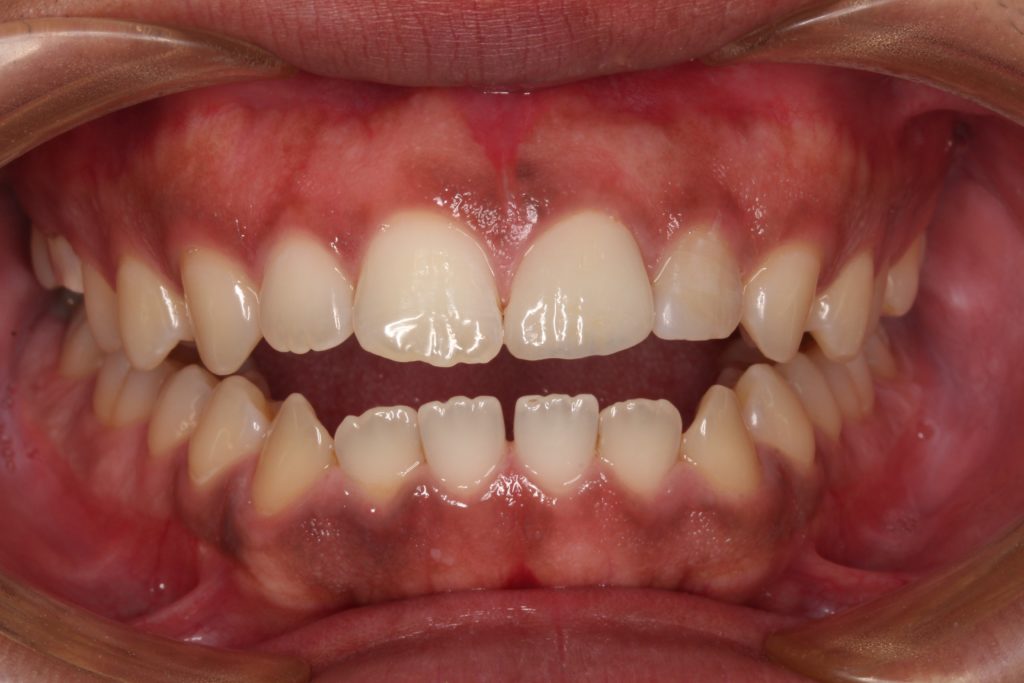

後日、専門の歯科技工が製作した歯をセットします。

クラウンがセットされた状態です。ジルコニアセラミッククラウンで仕上げています。

綺麗に歯が装着されています。

パッと見てどこを治療したのか分からないくらいに仕上がっていると思います。

色と形を反対側の歯に合わせ、周囲の歯にも馴染んでいます。